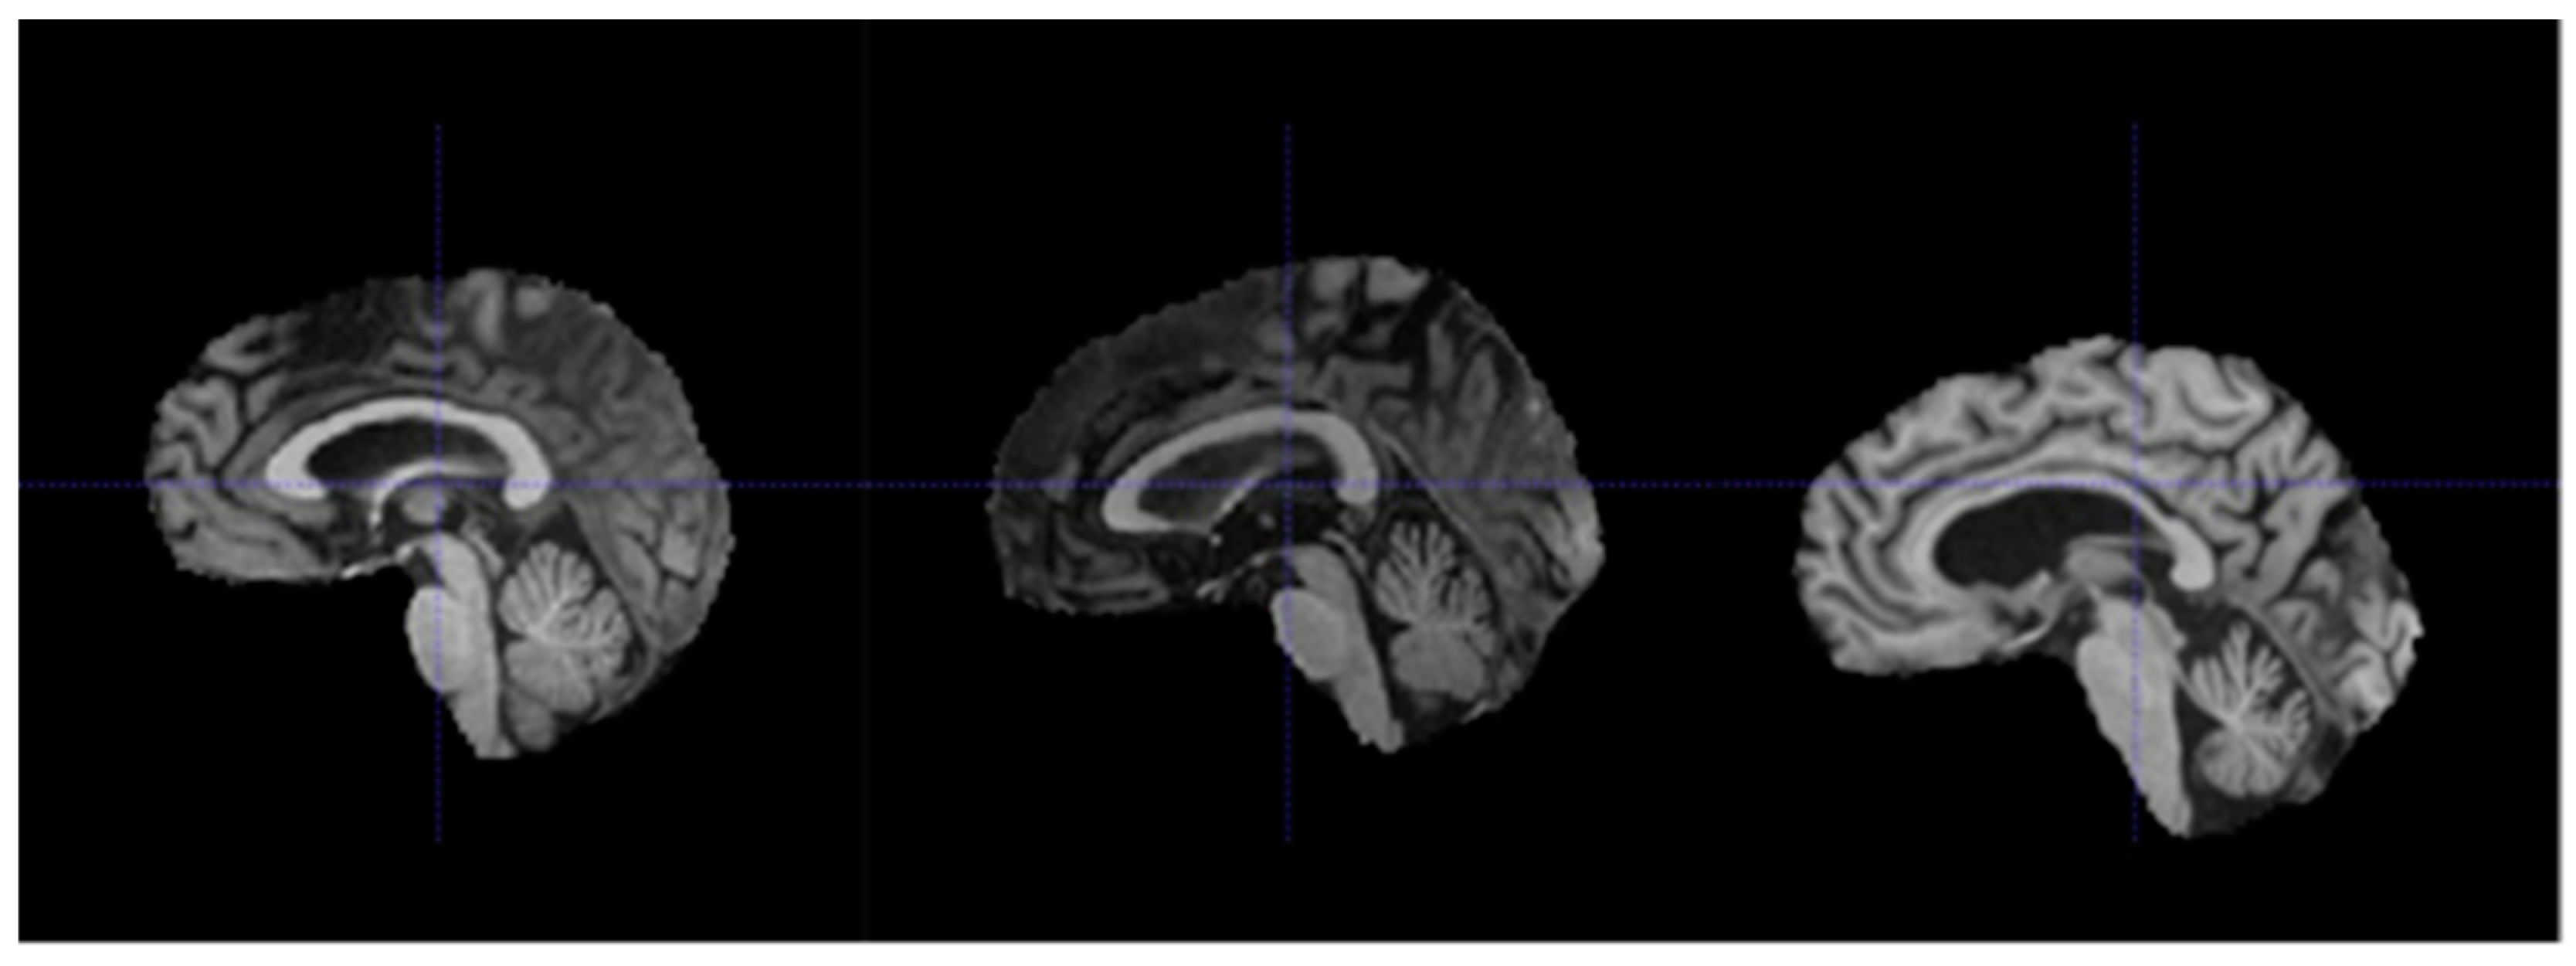

3.2. Data Preparation

- Re-orientation and registration: achieves good alignment of all MRI volumes.

- Field inhomogeneity correction: corrects abnormally dark or bright regions in the MRI volumes caused by inconsistencies in the magnetic field of the scanner.

- Non-brain tissue removal: removes irrelevant tissues such as that of the skull, eyes, and nose, leaving only the brain tissues in each volume.

- Intensity normalization: standardizes the intensities of each volume such that the same tissue types in each volume should have the same range of intensity values.